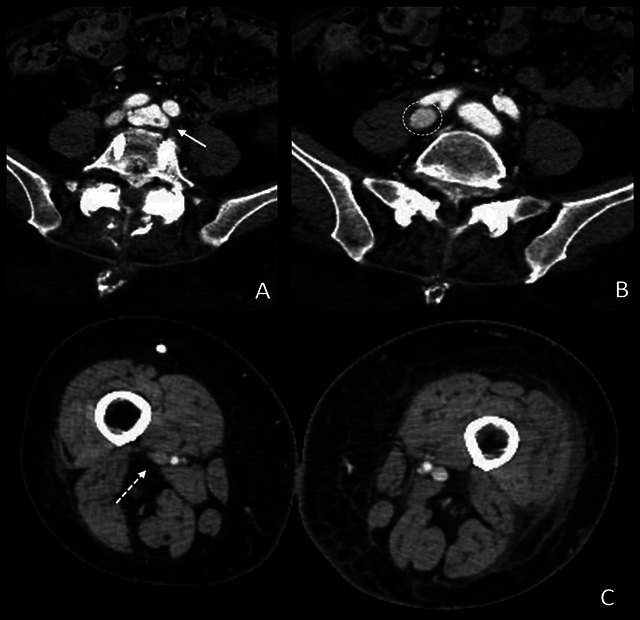

教学要点:虽然深静脉血栓是腰椎关节置换术后常见的并发症,但先天性动静脉瘘等罕见并发症也可能出现类似情况,这就凸显了广泛鉴别诊断和适当影像学检查对及时处理的重要性。

Teaching point: Although deep vein thrombosis is a common concern after lumbar arthrodesis, rare complications such as an iatrogenic arteriovenous fistula can present similarly, highlighting the importance of a broad, differential diagnosis and appropriate imaging for timely management.